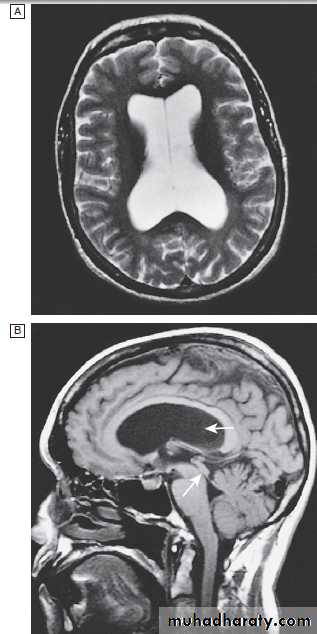

Cervical, thoracic and lumbar spine

Plain X-rays are useful in the investigation of trauma toVertebrae. MRI has transformed the investigation of these areas, since it can give information not only about the vertebrae and intervertebral discs, but also about their effects on the spinal cord and nerve roots.

Myelography is an invasive technique involving injection of contrast into the lumbar theca. While the outline of the nerve roots and spinal cord provides information about abnormal structure, the accuracy and wide availability of MRI have reduced the need for this.

Myelography may still be used for technical reasons or where MRI is unavailable, contraindicated, or precluded by the patient’s claustrophobia.

Different techniques of imaging the cervical spine. A Lateral X-ray showing bilateral C6/7 facet dislocation. B Myelogram showing

widening of cervical cord due to astrocytoma (arrows). C MRI showing posterior epidural compression from adenocarcinomatous metastasis to the posterior arch of T1 (arrows).